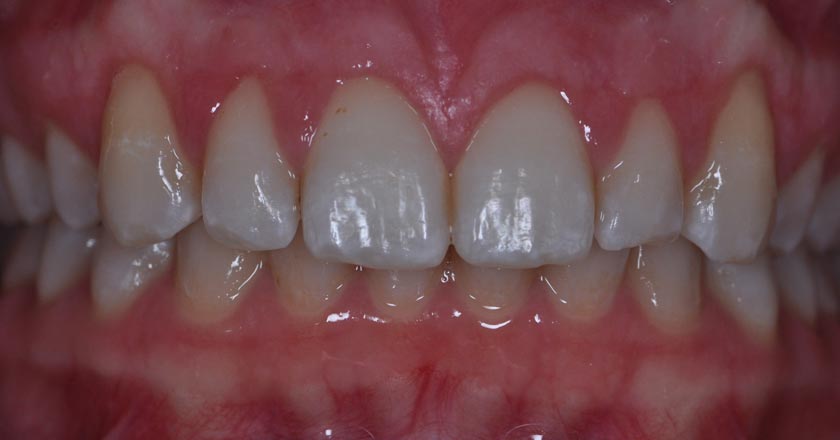

Gum Graft Upper - Before And After

Gum graft upper – after treatment